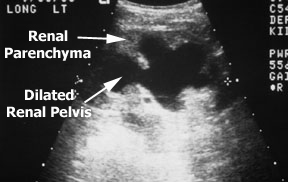

This longitudinal ultrasound of a left kidney shows a large hypoechoic area (black on an ultrasound means no echoes) in the center of the kidney. Notice how the dilation extends into the parenchyma. These areas are the calyces of the kidney. The normal hyperechoic area in the center of the kidney (the hilum) is replaced by a large hydronephrotic renal pelvis. This kidney has hydronephrosis due to obstruction of the upper ureter (additional studies revealed the location of the obstruction).